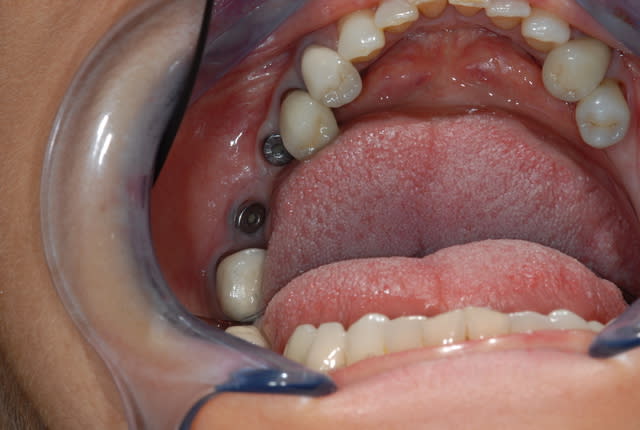

Bonjour à tous

je souhaiterai gagner de la gencive attachée en vestibulaire de 46 et 45 avant la pose des dents.

Dans le cas présenté, j avais fait extraction implantation de la 46 et pose de l implant en 45, la gencive n était pas terrible déjà, j ai gagné du conjonctif en 45 grâce à mon trace d incision mais pas en 46.

Je préfère pour cette raison, même après la pose des implants, améliorer le site et avoir un bandeau de gencive attachée avant de poser les dents.